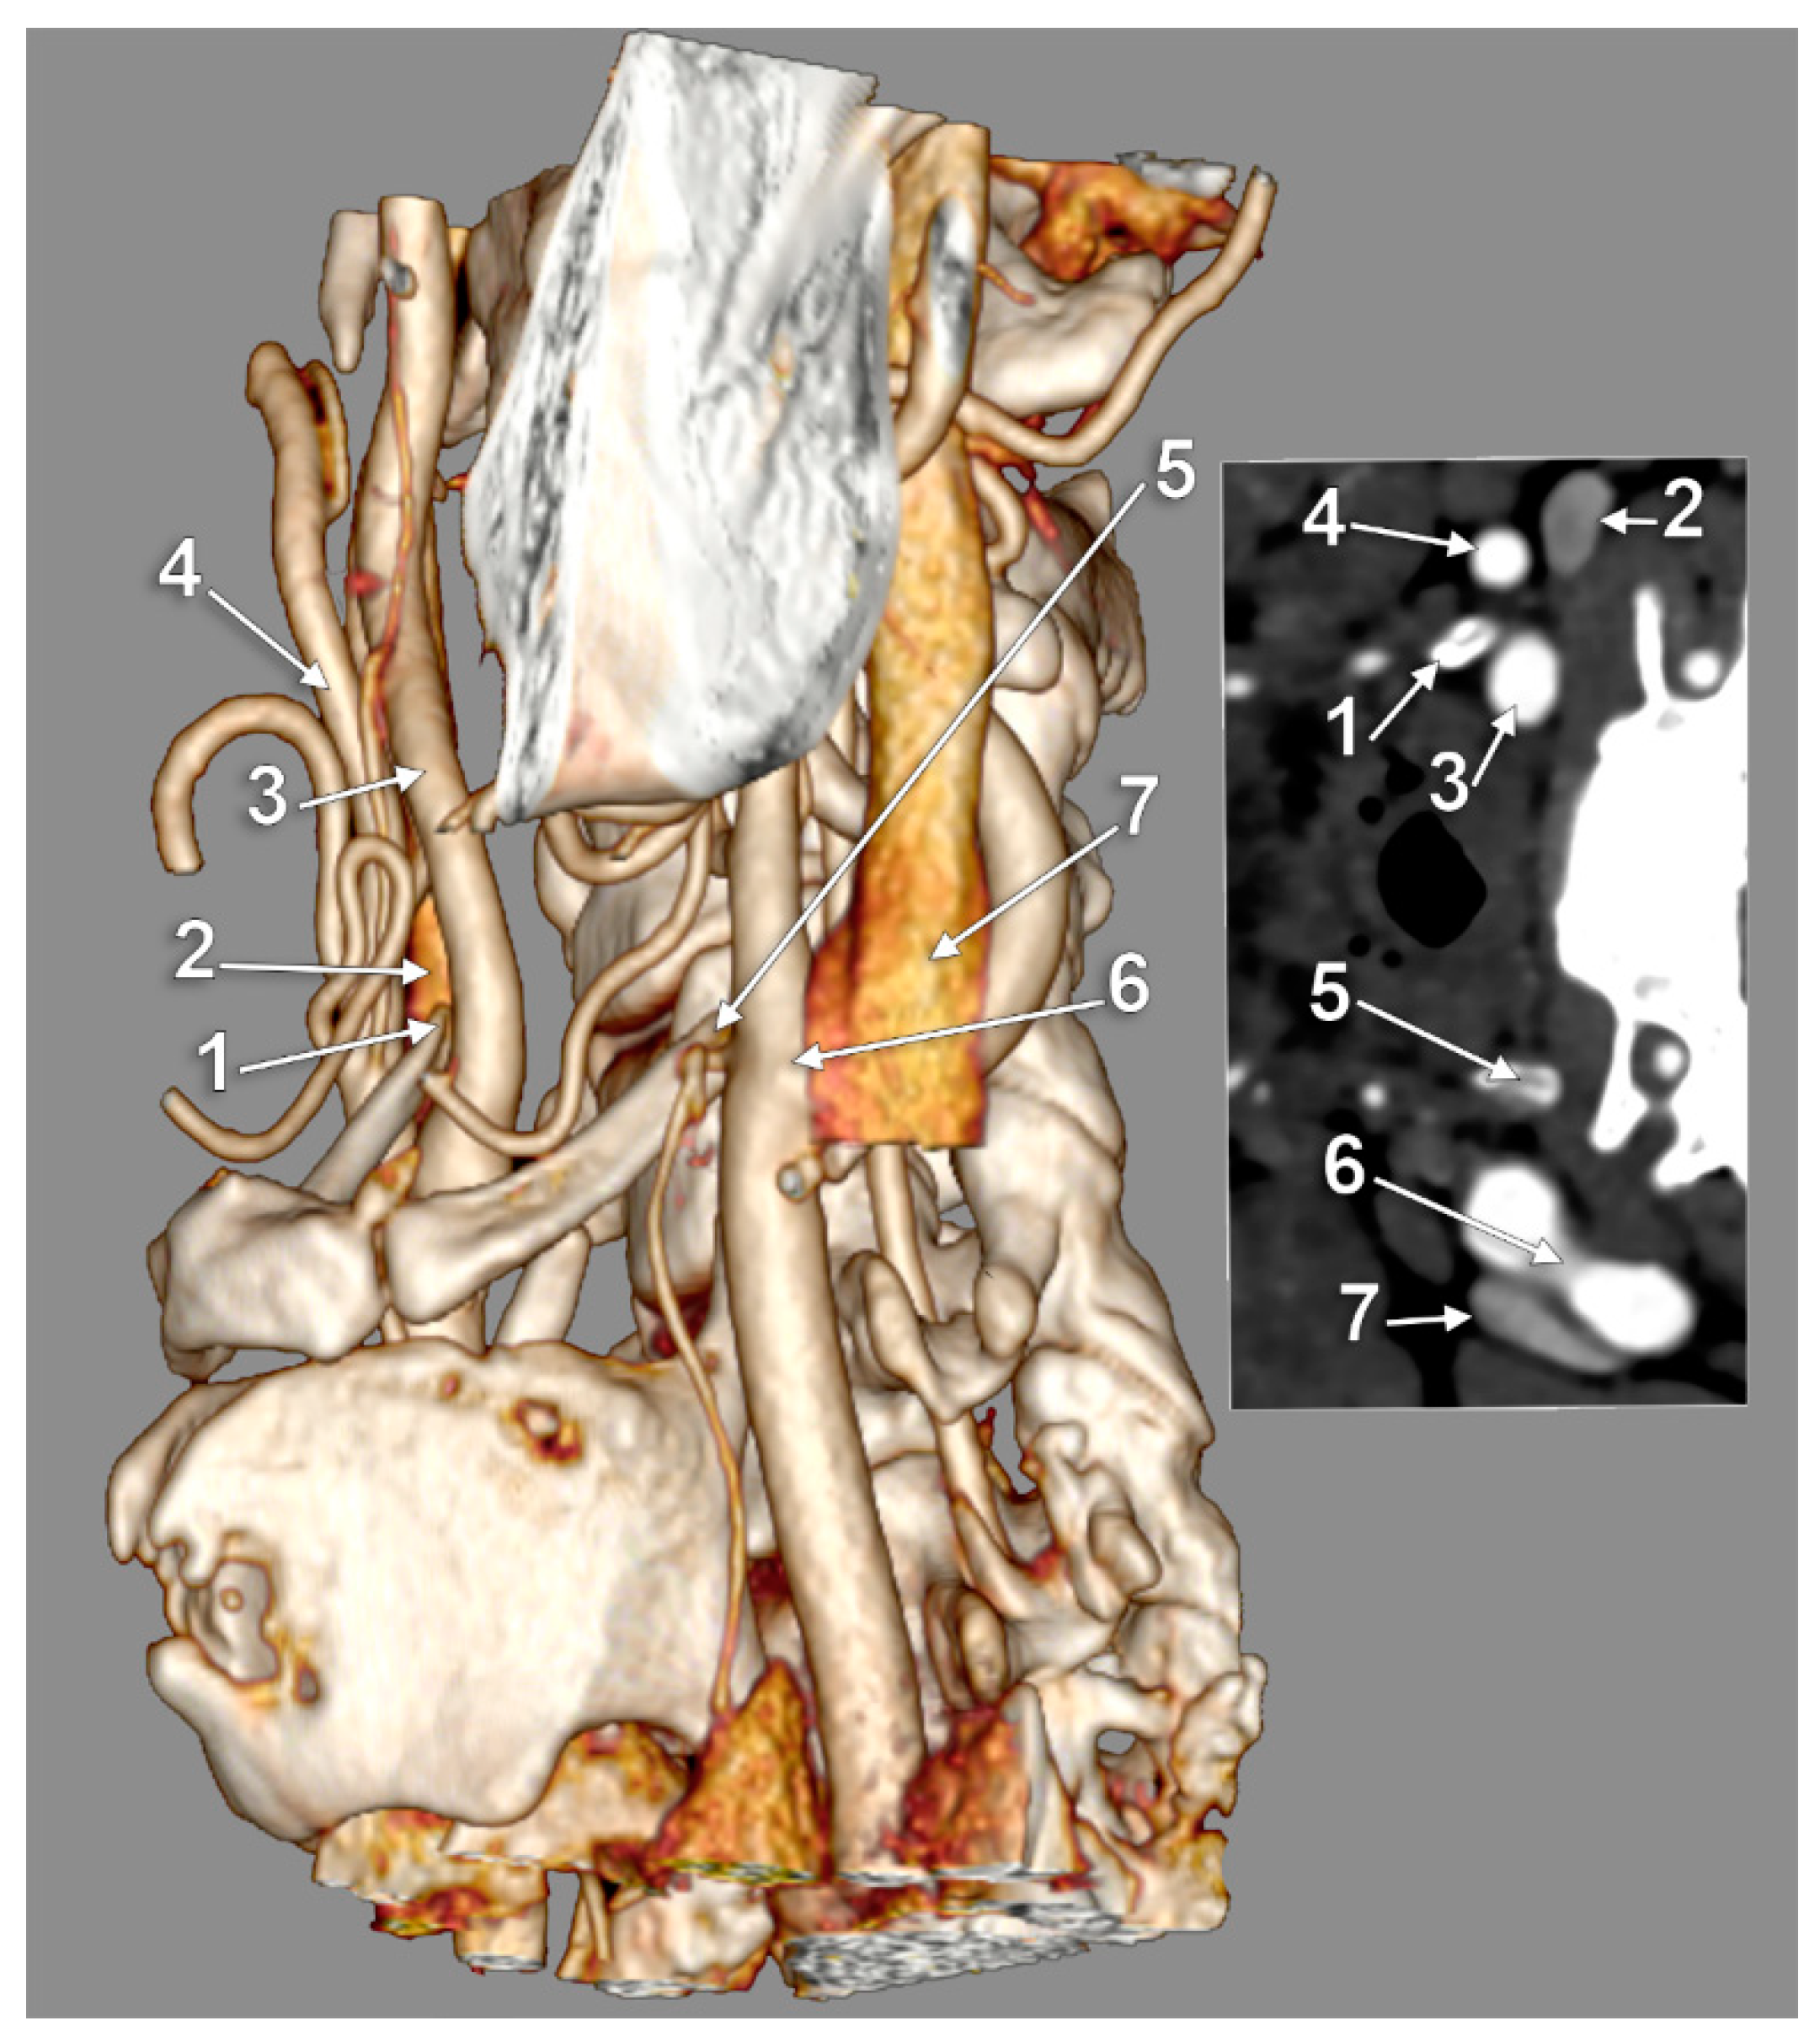

The Carotid–Hyoid Topography Is Variable

Manta, M.D.; Rusu, M.C.; Hostiuc, S.; Vrapciu, A.D.; Manta, B.A.; Jianu, A.M. The Carotid–Hyoid Topography Is Variable. Medicina 2023, 59, 1494. https://doi.org/10.3390/medicina59081494